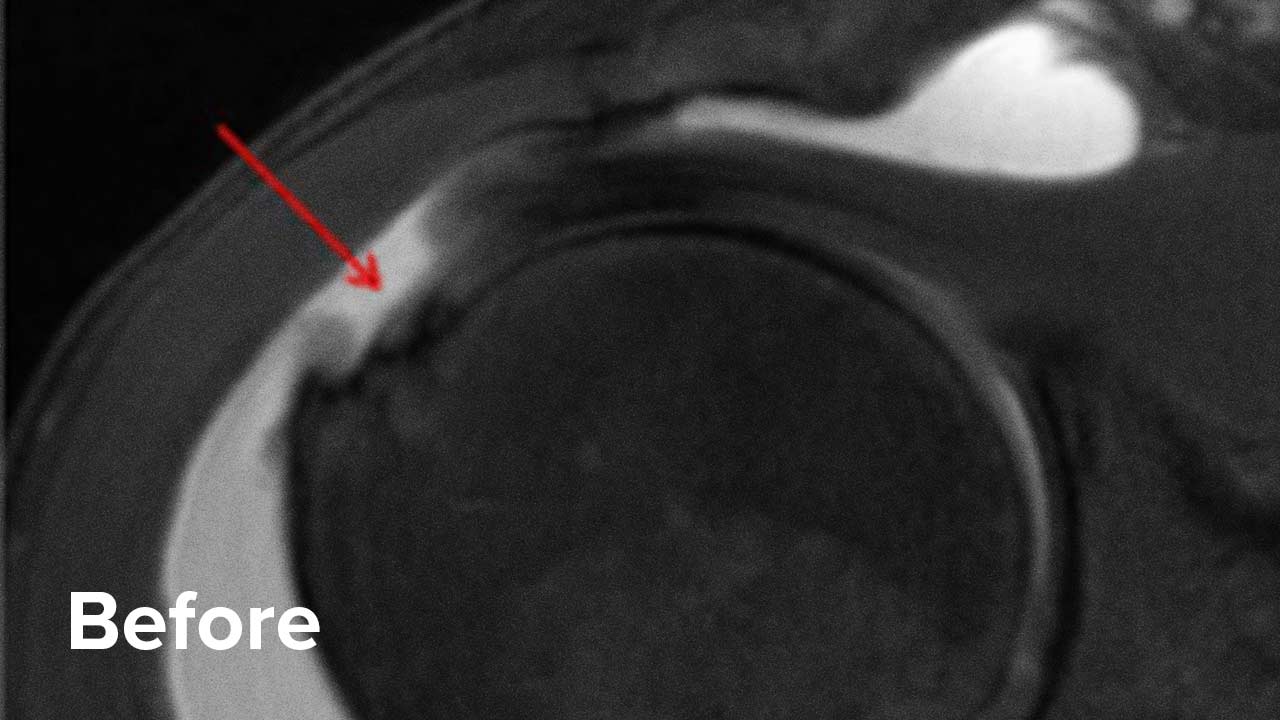

Before and After Shoulder Repair MRI Images

Take a look at the outcomes of two of our patients who chose to have a Regenexx procedure instead of surgery.

Scroll the arrow to the right to see the MRI of the rotator cuff before the treatment and to the left to see the outcome. The BEFORE shows a torn rotator cuff. The arrow points at a gap where the tendon should be. Once treated, the area will look like a dark band going diagonally, as seen on the AFTER.

Patient 1 MRI